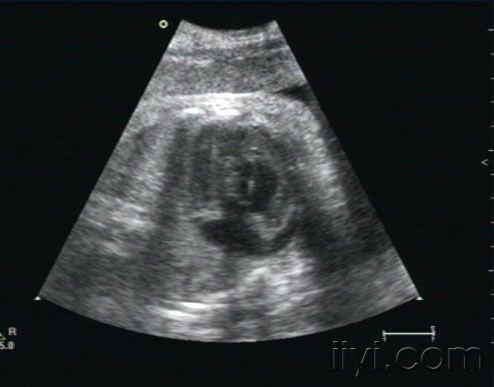

胎儿心包积液

• 孕38周,10天以前在多家医院检查胎儿正常。近一周来自觉腹胀,下坠。发现胎儿心包积液,并且右室壁好象很厚。胎儿生下来后,临床医生没有听到杂音,遗憾的是孩子也没来检查心脏。我们没有开展胎儿心脏,请各位专家帮忙看下,到底是什么原因,胎儿右室壁增厚考虑什么病,为什么生后没有杂音呢?